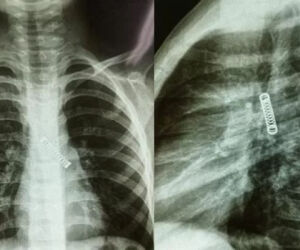

Os pais de uma criança de 5 anos resolveram procurar ajuda médica após seu filho apresentar, desde dezembro de 2022, uma tosse constante, porém, o que os médicos encontraram durante um exame de raio-x chamou a atenção, já que foi encontrada uma mola presa no pulmão esquerdo do garoto.

Em entrevista ao jornal The Mirror, o médico responsável pela cirurgia de retirada do objeto, Carlos Morinigo, disse que a criança deve ter engolido a mola, não respirado, e que o tempo que ela passou alojado no pulmão do garoto causou danos, porém, esses estragos devem melhorar conforme a criança envelhecer.